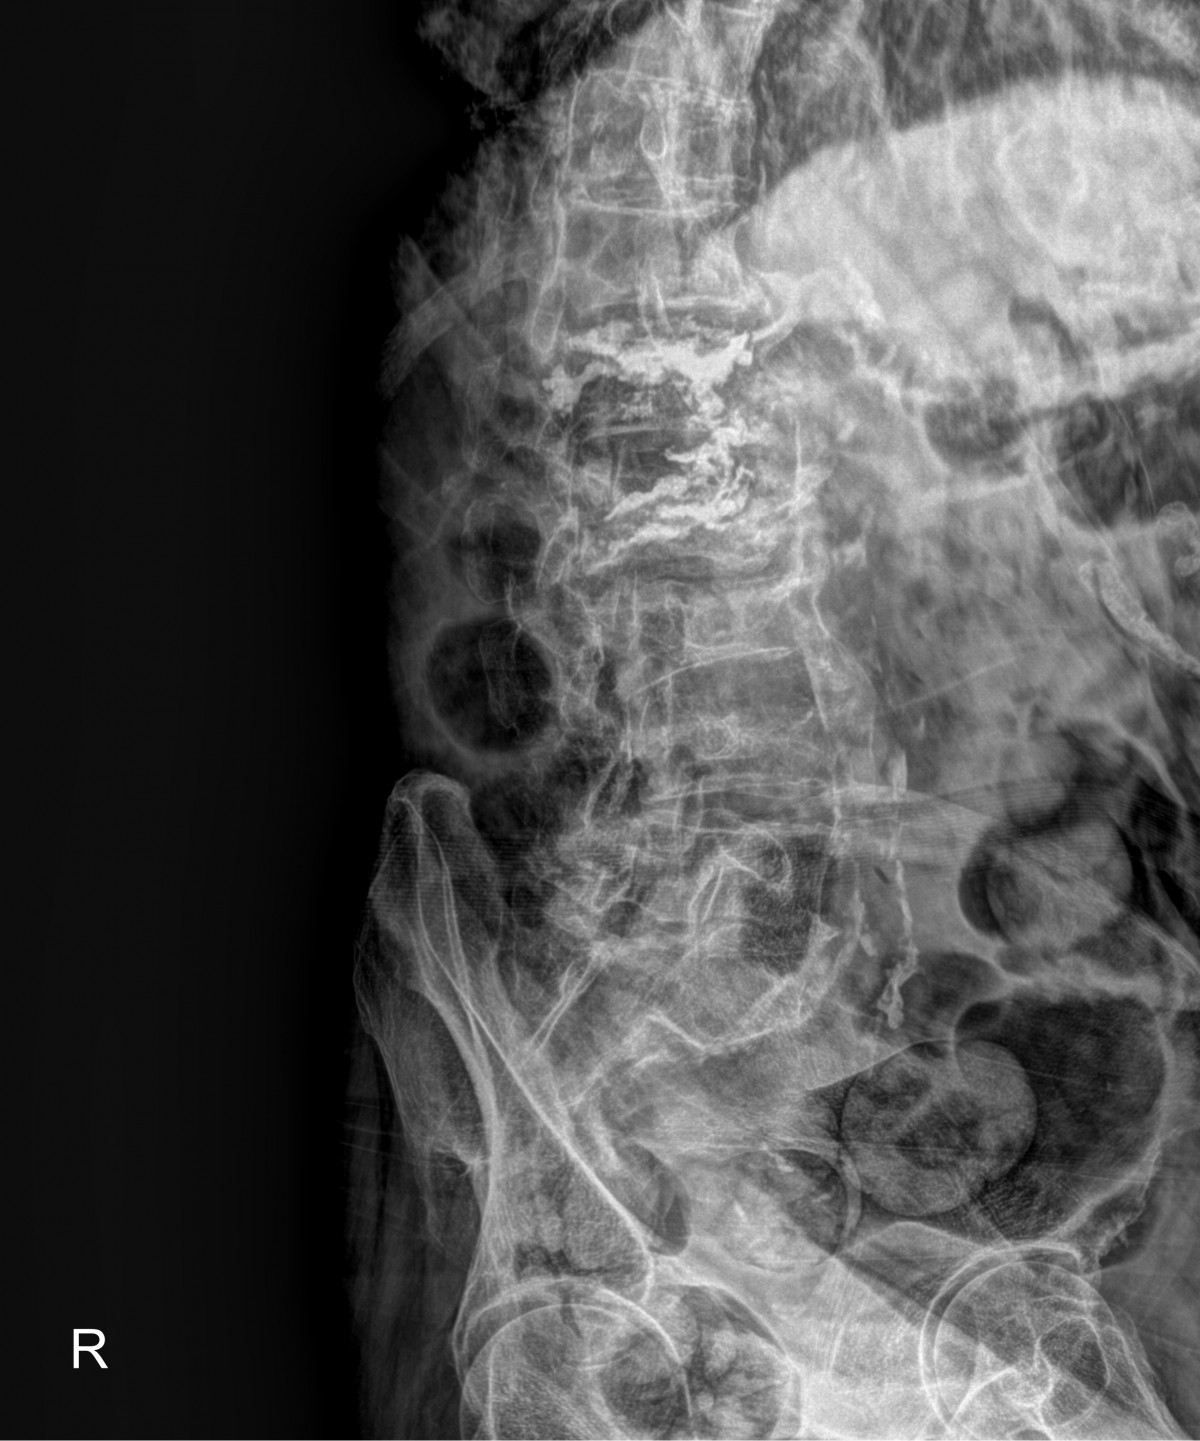

정지영원장님 허리 골절 골시멘트 성형술 김창O 환자

dae765e4d9ac96aee867c9d6292d8784_1758007966_426.jpg